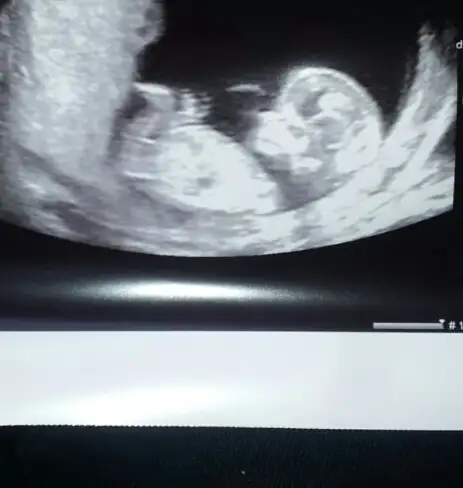

%99 erkek canımbakın teyzeleri tahminleri alayım :))

Bariz erkek pipiye bakbakın teyzeleri tahminleri alayım :))

Az önce ultrasonda n çıktım 13+4

Doktorum cinsiyet kesin değil ama kız gibi dedi sizlerden yorum bekliyorum lütfen ☺☺Eki Görüntüle 1468173